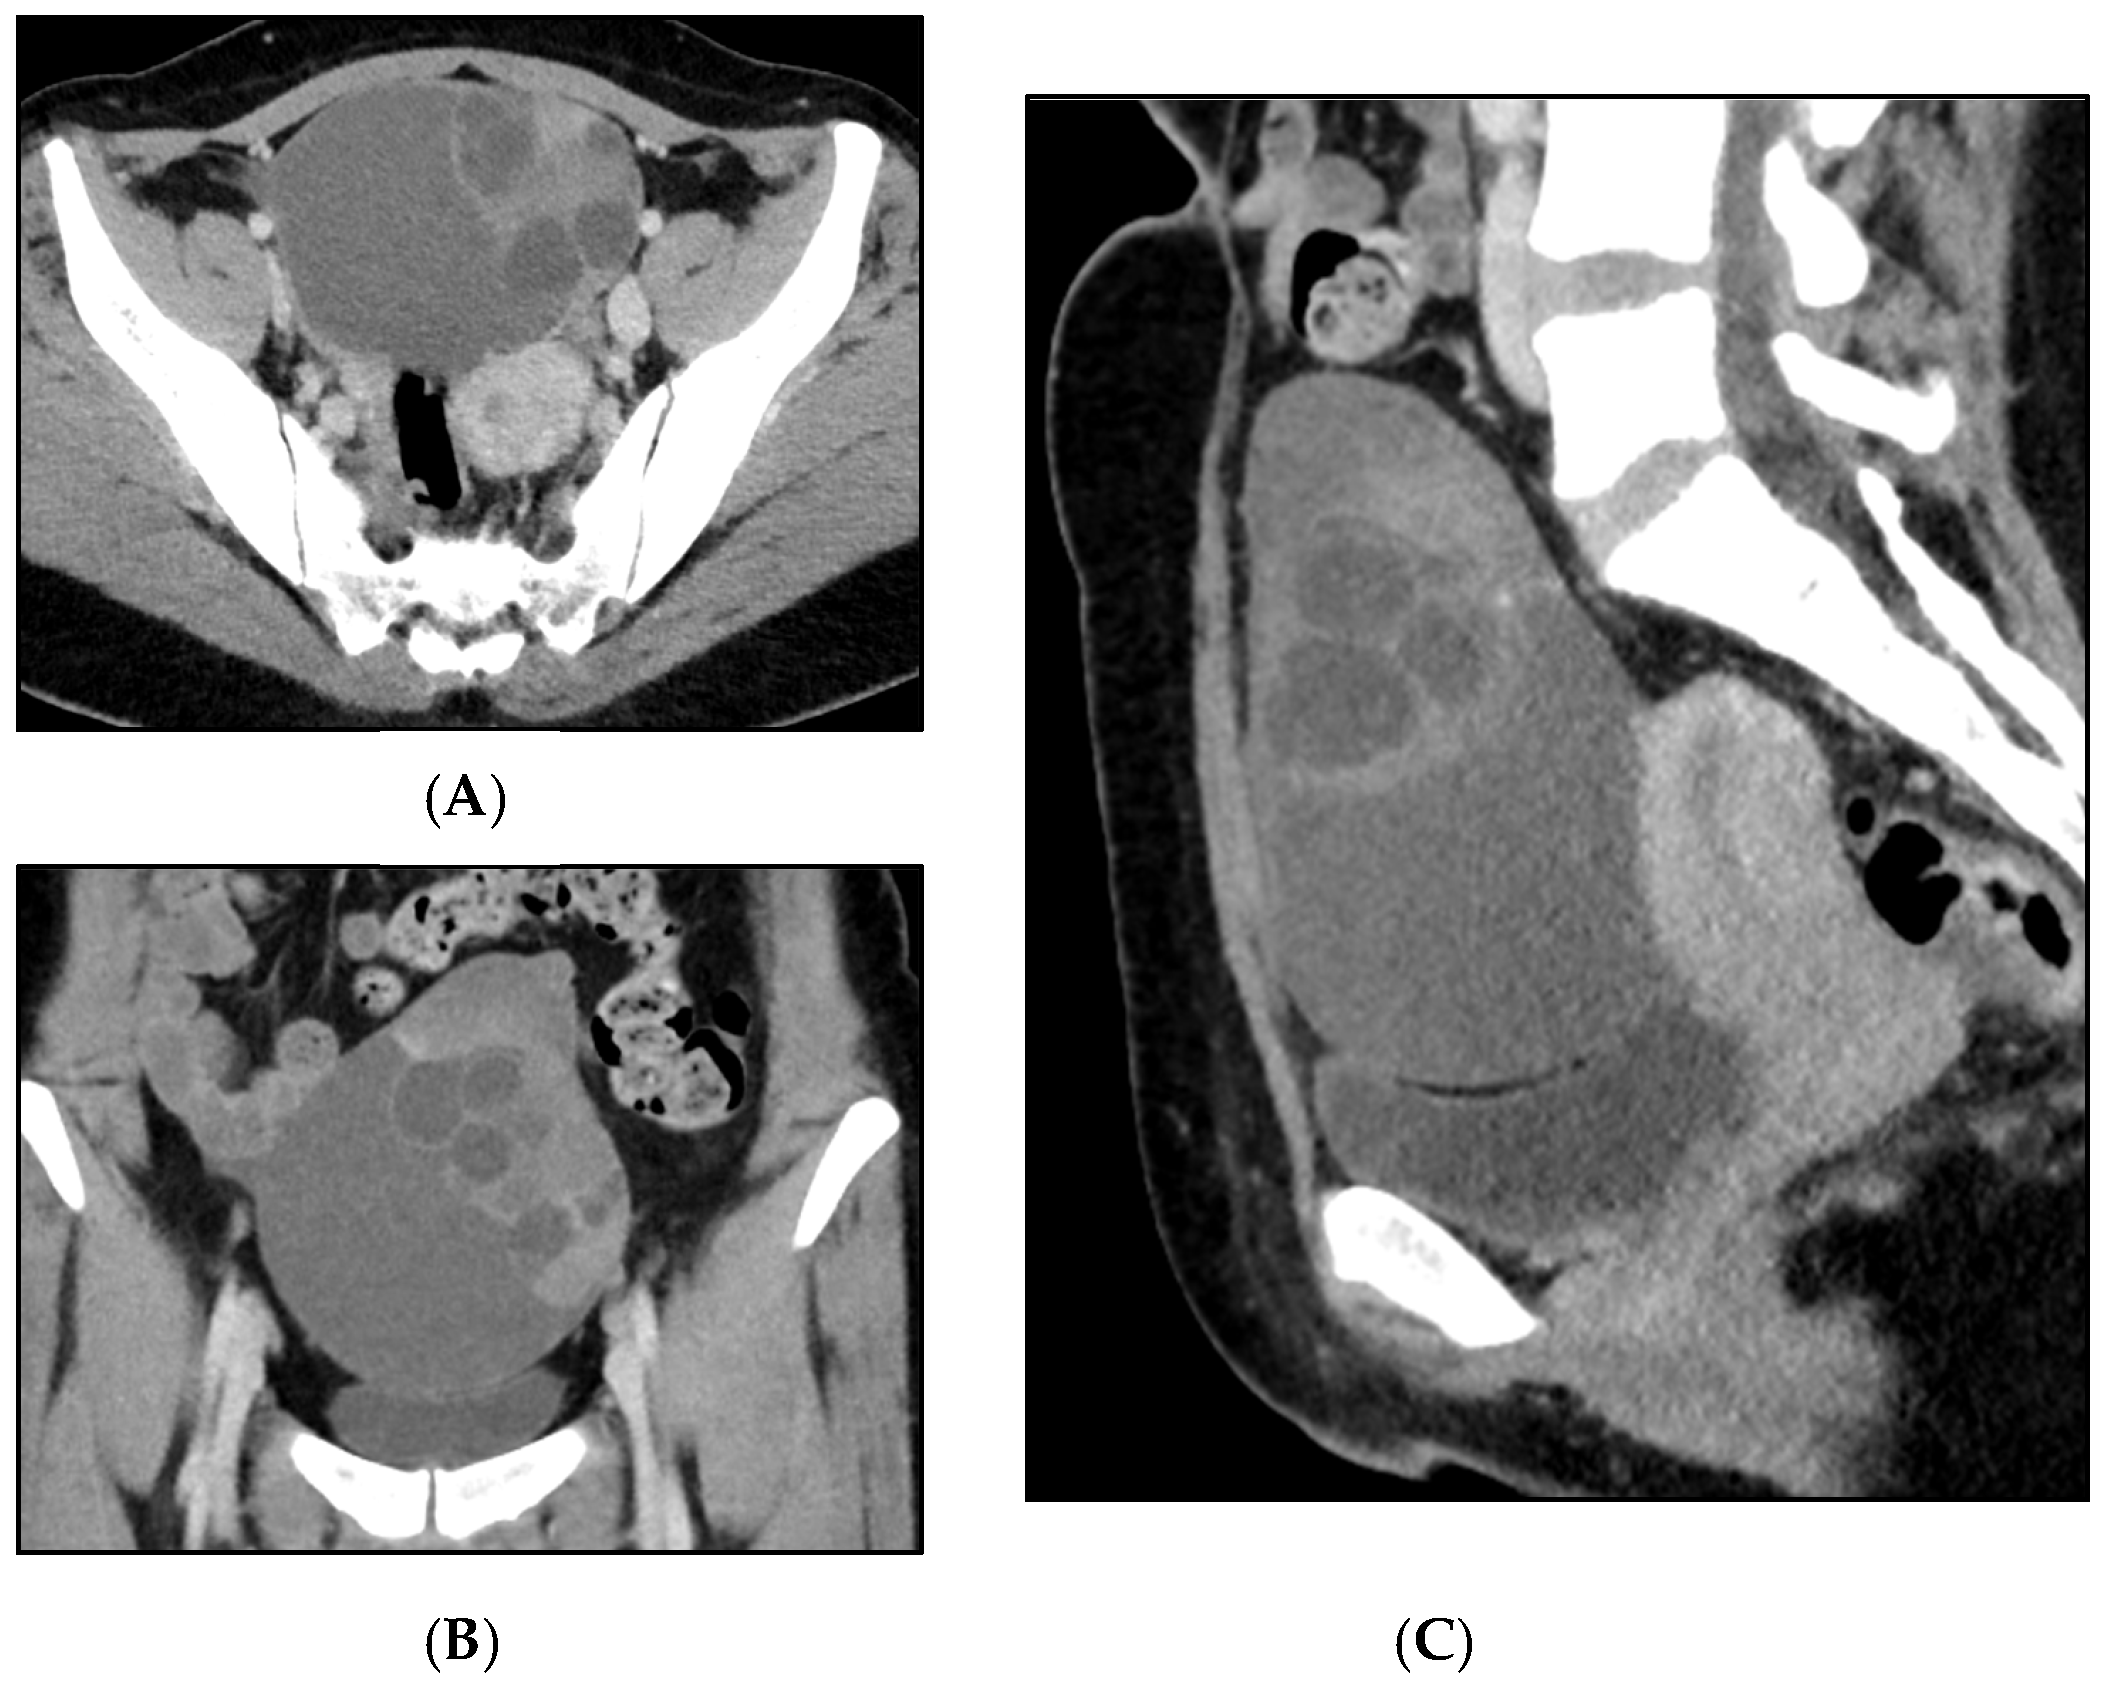

Mucinous Carcinoma, Mucinous Borderline Tumor and Pseudomyxoma Ovarii in a Cystic Teratoma: A Histological Conundrum

Giacometti, C.; Mirandola, M.; Aliberti, C.; Molinari, F.; Marcolini, L.; Mautone, D.; Martignoni, G. Mucinous Carcinoma, Mucinous Borderline Tumor and Pseudomyxoma Ovarii in a Cystic Teratoma: A Histological Conundrum. Diagnostics 2025, 15, 1957. https://doi.org/10.3390/diagnostics15151957